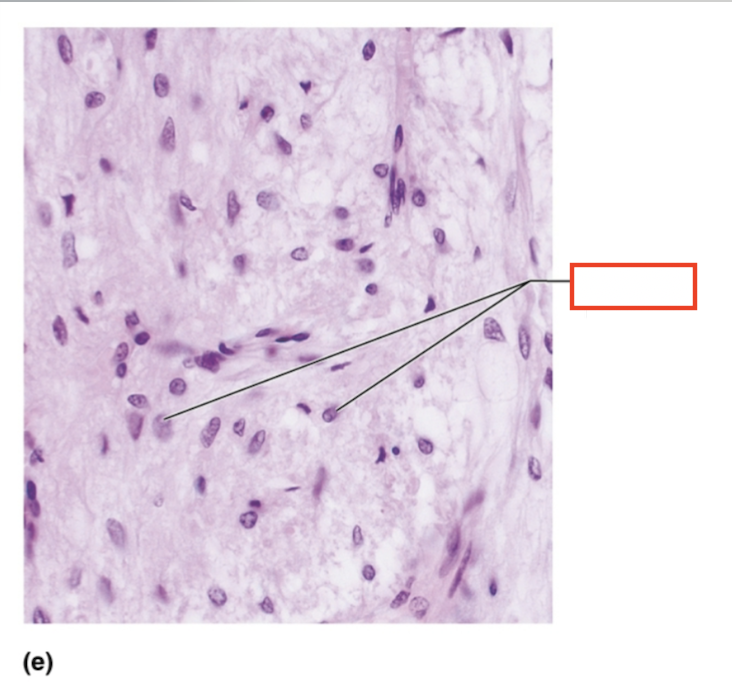

acidophils

What structure is highlighted?

chromophobe

What structure is highlighted?

basophil

What tissue is shown?

anterior pituitary

What hormones are released by the anterior pituitary gland?

TSH, FSH, LH, ACTH, GH, PRL

What are the tropic hormones?

TSH, FSH, LH, ACTH